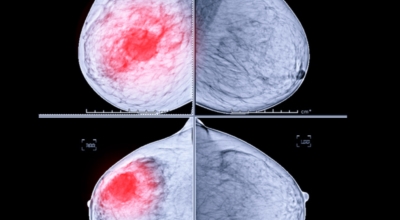

유방암이란?

유방 밖으로 퍼진 악성 종양으로 생명을 위협할 수 있어요. 유방암은 보통 유방의 유관과 소엽에서 생기는데요 남성도 드물게 유방암에 걸릴 수 있어요. 유방암은 아직 명확한 원인이 알려지지 않았어요. 하지만 여러 가지 위험 요인을 추정할 수 있는데요 유전, 호르몬, 노화, 음주, 비만 등이 있답니다. 가장 흔한 증상은 유방에 발생하는 종괴입니다. 그리고 유두 분비, 유방통, 피부궤양, 함몰, 겨드랑이 종괴 등이 나타날 수 있어요. 증상들이 꼭 유방암을 나타내는 것은 아닐 수도 있으므로 정확한 검사가 필요하다고 해요.